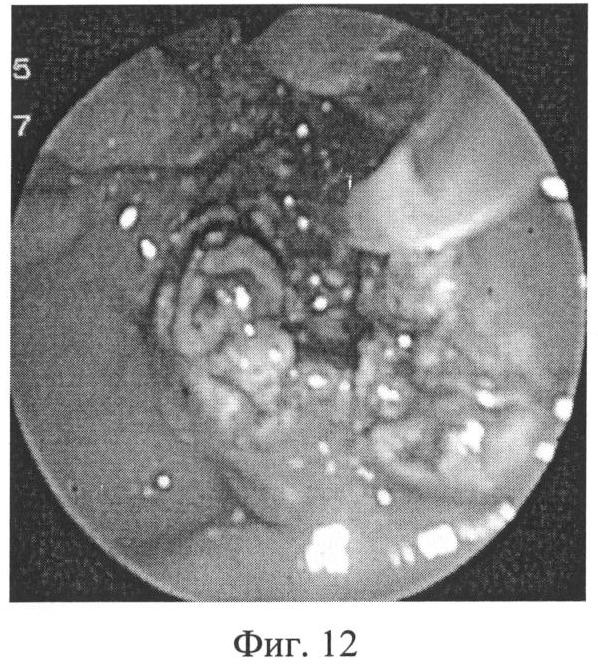

На эндоскопических фотографиях (фиг.6-12) наглядно представлены этапы операции эндоскопической папиллотомии предложенным новым нетипичным способом – крестообразным разрезом.

Фиг.12 – после поперечного разреза канюляция пересеченной трубчатой структуры (узкий холедох) успешна, что подтверждается фиг.13.